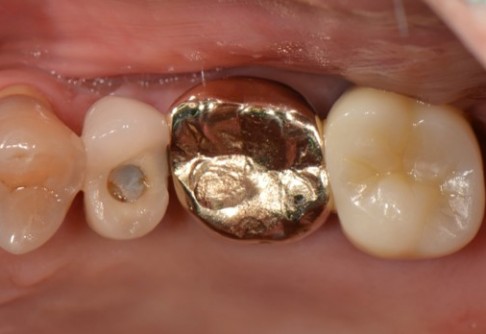

Before

After

위 치료 사례는 굿프렌즈치과에서 직접 치료를 받은 환자 분의 사례로 직접 동의를 얻어 게재되었습니다.